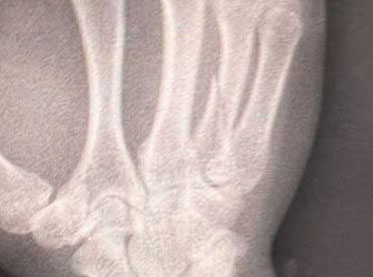

YUSHIの骨折部分(YUSHITwitterより)